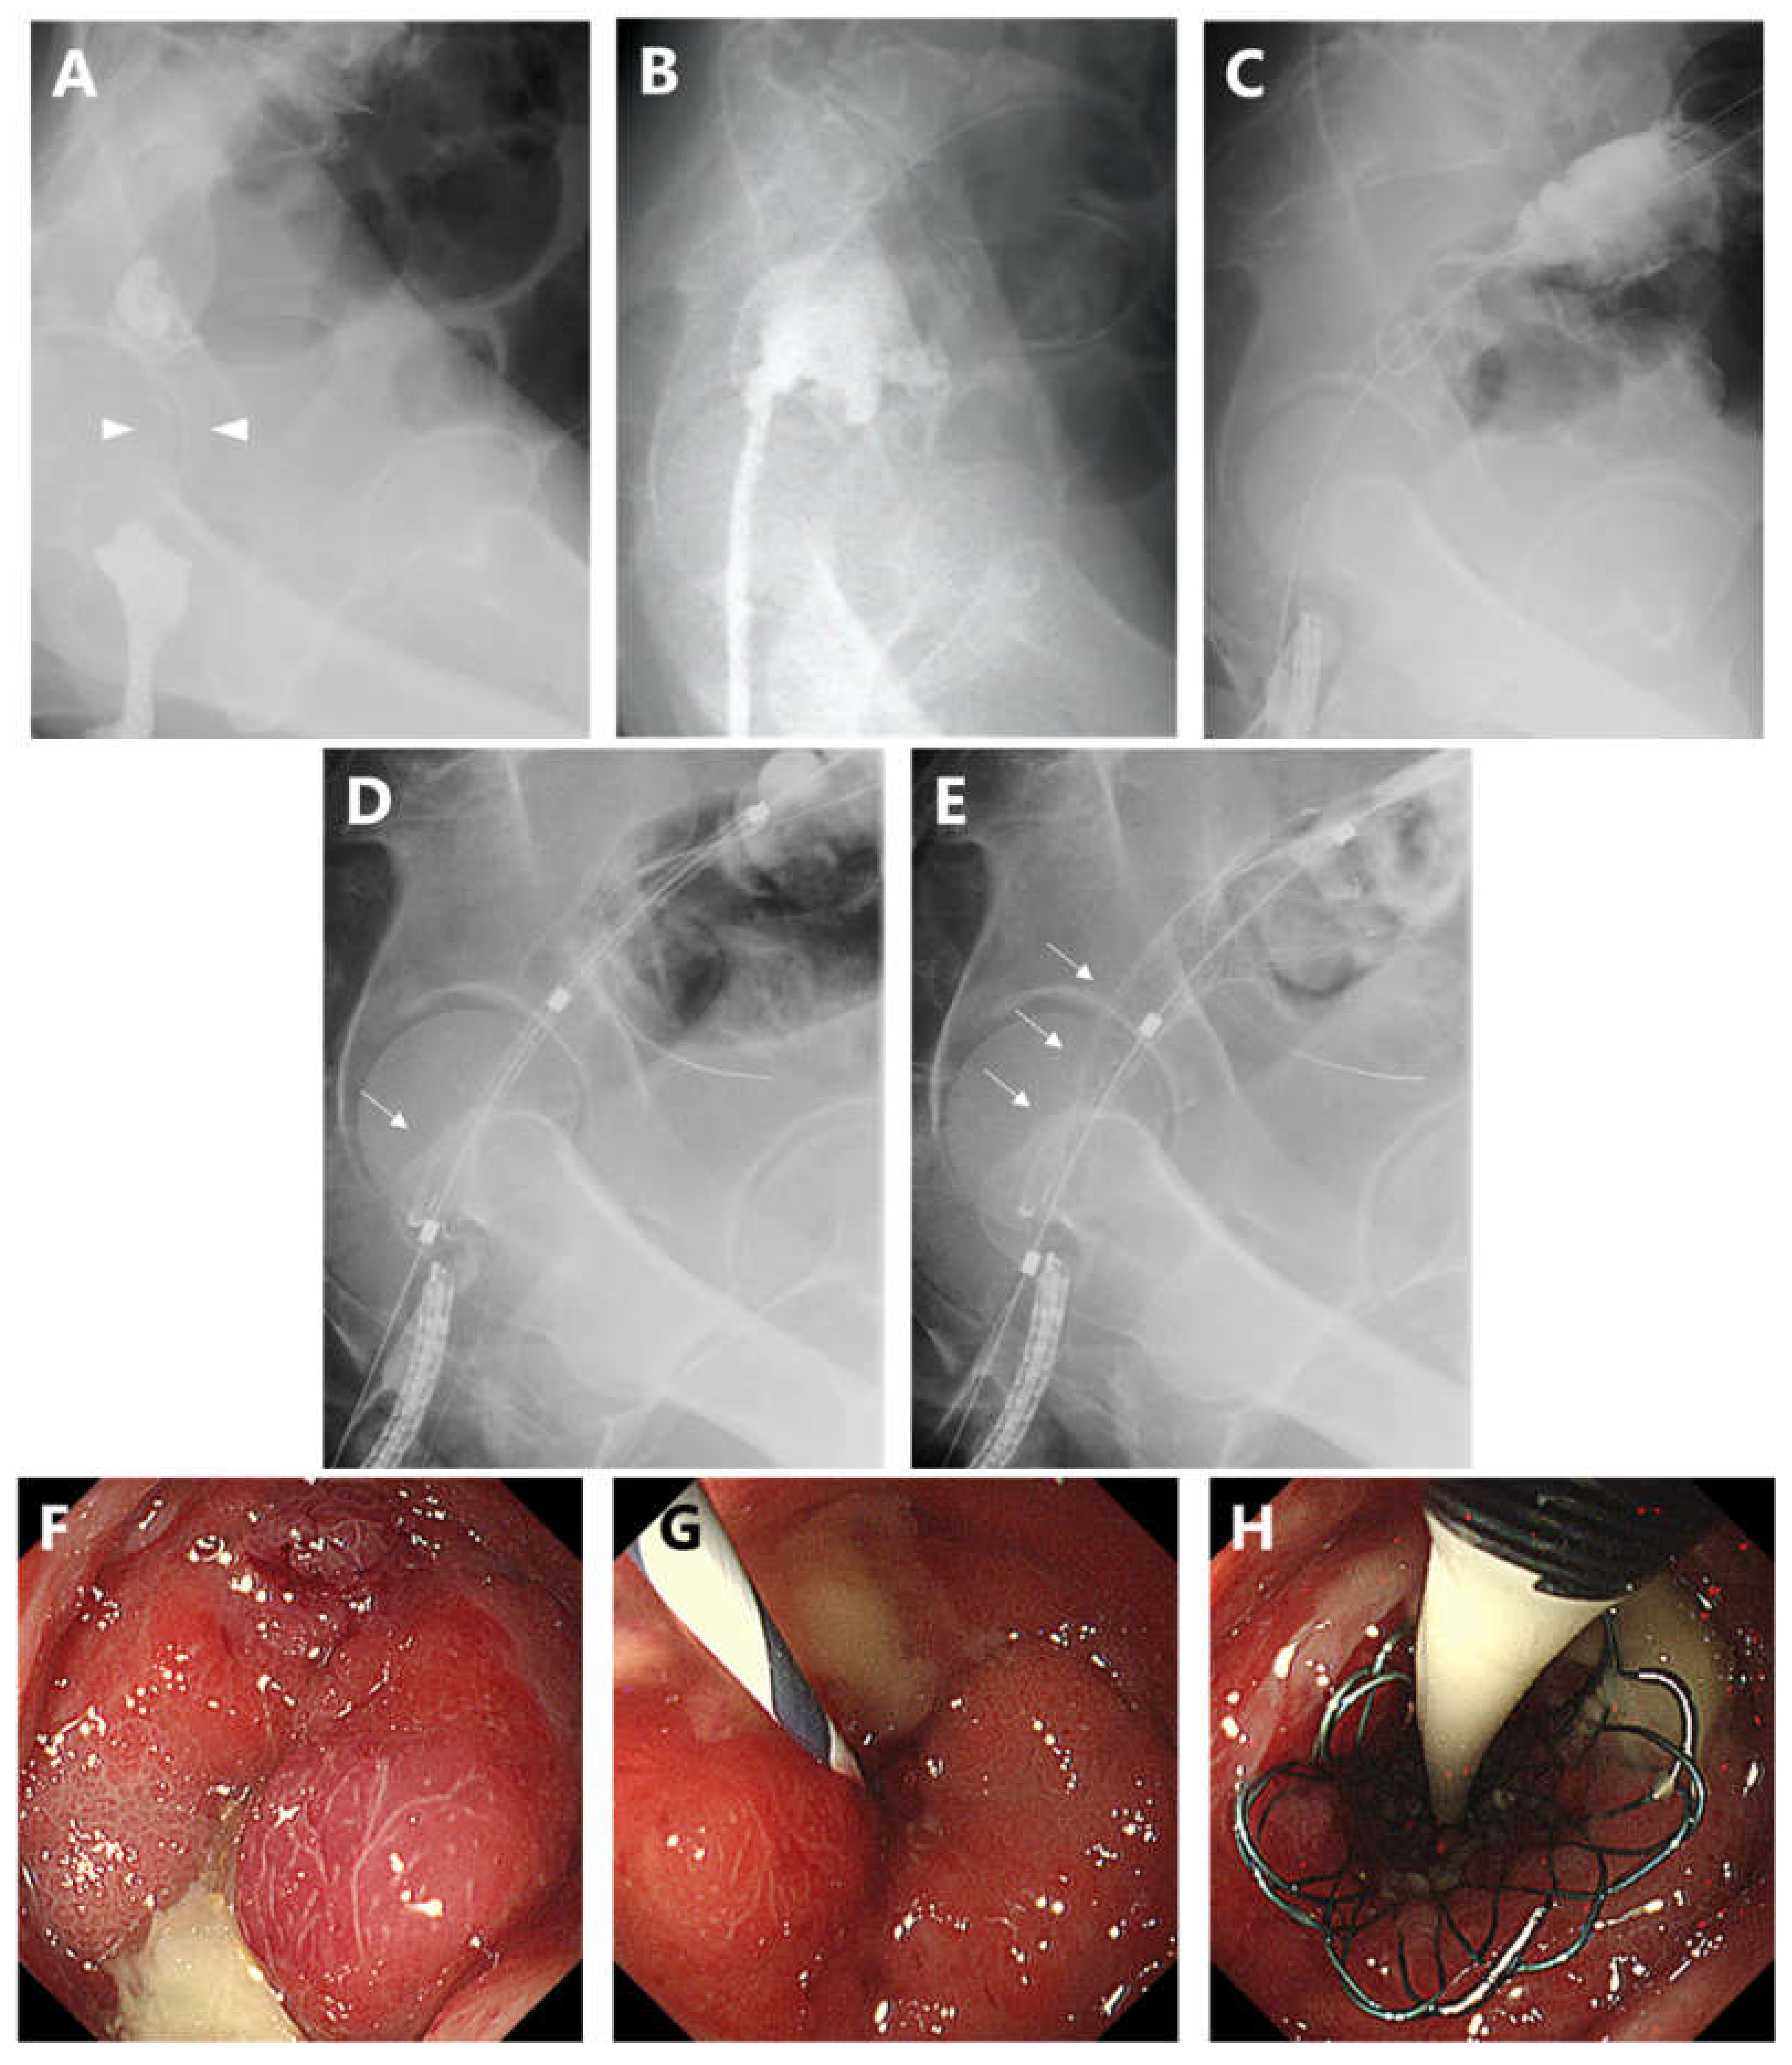

- Tao, K.; Kuwai, T.; Ishaq, S.; Enomoto, T.; Saida, Y. Newly developed proximal release–type colonic stent placement for malignant lower rectal obstruction. VideoGIE 2020, 5, 250–251. [Google Scholar] [CrossRef]